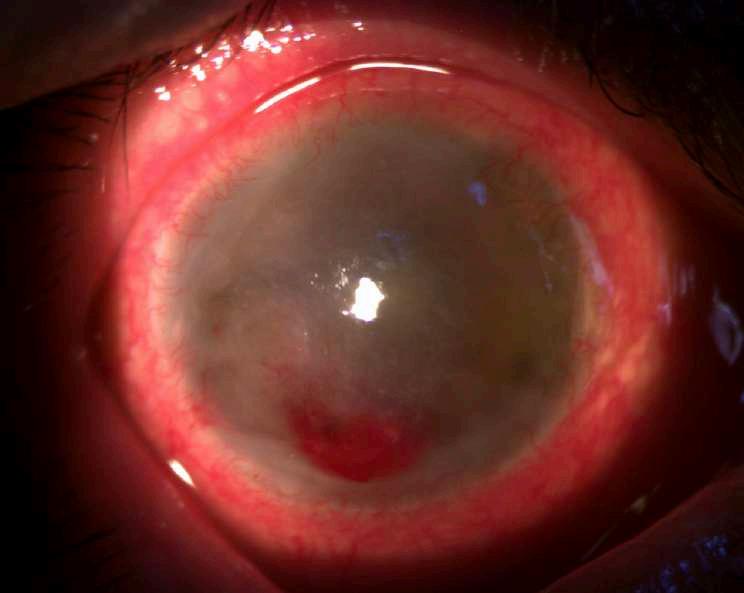

3.B. MELANOMA AMELANÓTICO

Caso aportado por Dr. Osvaldo Weisse

ü Imagen C: Lesión sólida ligeramente irregular, homogénea, de reflectividad media baja con elementos de vascularidad en su interfase. Altamente consistente con melanoma de coroides

ü Mujer 57 años consultó en policlínico por cuadro de disminución de la agudeza visual de hemicampo superior del ojo derecho, indoloro de 1 mes de evolución

ü Imagen B: Subyacente al DR hay una lesion sólida dependiente de la coroides, irregular en base (18.8mm) y altura (1.63)

C

A B

OSORIO CARPIO, GLORIA

Female 10/11/1962 8022643-8

Exam Date:

Exam Time:

Serial Number: 5000-2474

Technician:

Name: 2/10 9:21 2/26/2020

Tecnologos, HDS

Signal Strength:

High Definition Images: HD 5 Line Raster

HOSPITAL DEL SALVADOR

Length:

Spacing: Scan Angle: 9 mm 0.25 mm 9°

ü Imagen D y E: Lesión coroidea que levanta la macula, asociada a líquido subretinal

Comments

OS OD

D E